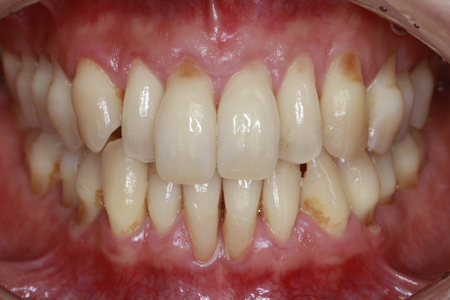

下がった歯茎を美しく、強く再生|

30代 男性

矯正治療と根面被覆術による口腔環境の改善

治療名 【審美・機能回復】歯肉退縮に対する根面被覆術+マウスピース矯正 治療期間 約1年 執刀医 Dr. 大杉 治療費 1,150,000円(税込)

■内訳:

矯正治療 900,000円

オペ費用 250,000円治療解説 歯肉退縮の改善と、将来的に歯を失うリスクを下げる目的で治療を行いました。

まずマウスピース矯正で歯列と噛み合わせを整えたうえで、結合組織移植による根面被覆を実施。

見た目だけでなく、歯を長く残すための安定性も重視して回復を図りました。リスク・副作用 歯の移動時に数日程度の違和感や疼痛が生じることがあります。

術後の過度なブラッシング圧や不適切な清掃用具の使用は、再度の歯肉退縮(再発)を招く主原因となるため、適切なケア指導の遵守が必要です。 -